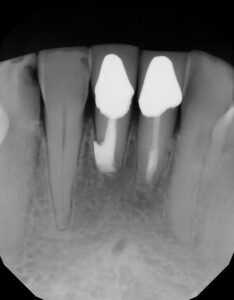

At three weeks post op, area is feeling better, inflammation/infection has resolved, tissue looks improved and both teeth are class II mobile.

From this point, the patient has remained asymptomatic and we have seen full resolution of PARL.